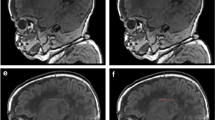

Significantly lower fractional anisotropy and higher radial diffusivity values were found in the centrum semiovale, corona radiata, posterior limb of the internal capsule, and arcuate fasciculi in infants with PWML (Fig. 4). Many but not all of these brain regions intersect with the locations of PWML. Greater lesion load was associated with higher radial diffusivity (R2 = 0.10 p < 0.001) and lower fractional anisotropy (R2 = 0.11 p < 0.001) in regions of the corona radiata and posterior limb of internal capsule.

Punctate white matter lesions are associated with altered white matter microstructure. Mean fractional anisotropy maps in sagittal, coronal, and transverse views showing white matter regions where infants with punctate lesions had significantly (A). higher radial diffusivity (blue) and (B). lower fractional anisotropy (green) as assessed with tract-based spatial statistics.